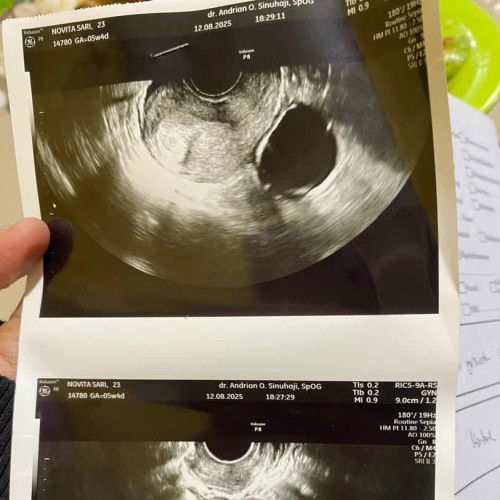

Ternyata aku punya kista

usg di usia kandungan 5minggu karna ngflek coklat khawatir kehamilannya knpa2 ternyata pas di cek aku punya kista 4,7cm 😭 dan kehamilannya blm ada kantung janin yaallah aku makin panik soalnya ngeflek uda 4hari (sedikit2) disuruh dokter balik lagi bulan depan kayanya ini sebulan terlamaku 🥹🥹

sama aku jg awal pemeriksaan di 4 week 5hari trnyata ada kista tpi ukurannya kurang dari 2 cm.. kata dokter selama ukurannya di bawah 5cm msih aman.. nnti jg bisa keluar sendiri klo lahiran. jaga pola makan biar yg membesar janinnya